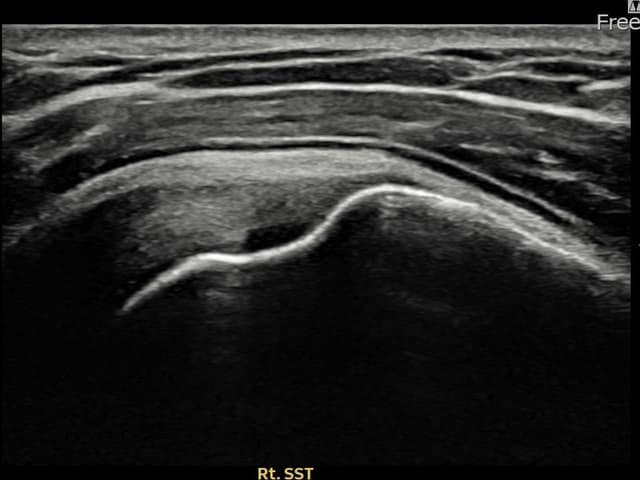

[촬영시기:22.09.19~22.12.09]

[어깨인대 축소봉합술] 우측 어깨 통증이 수개월간 지속되어 내원하셨습니다.